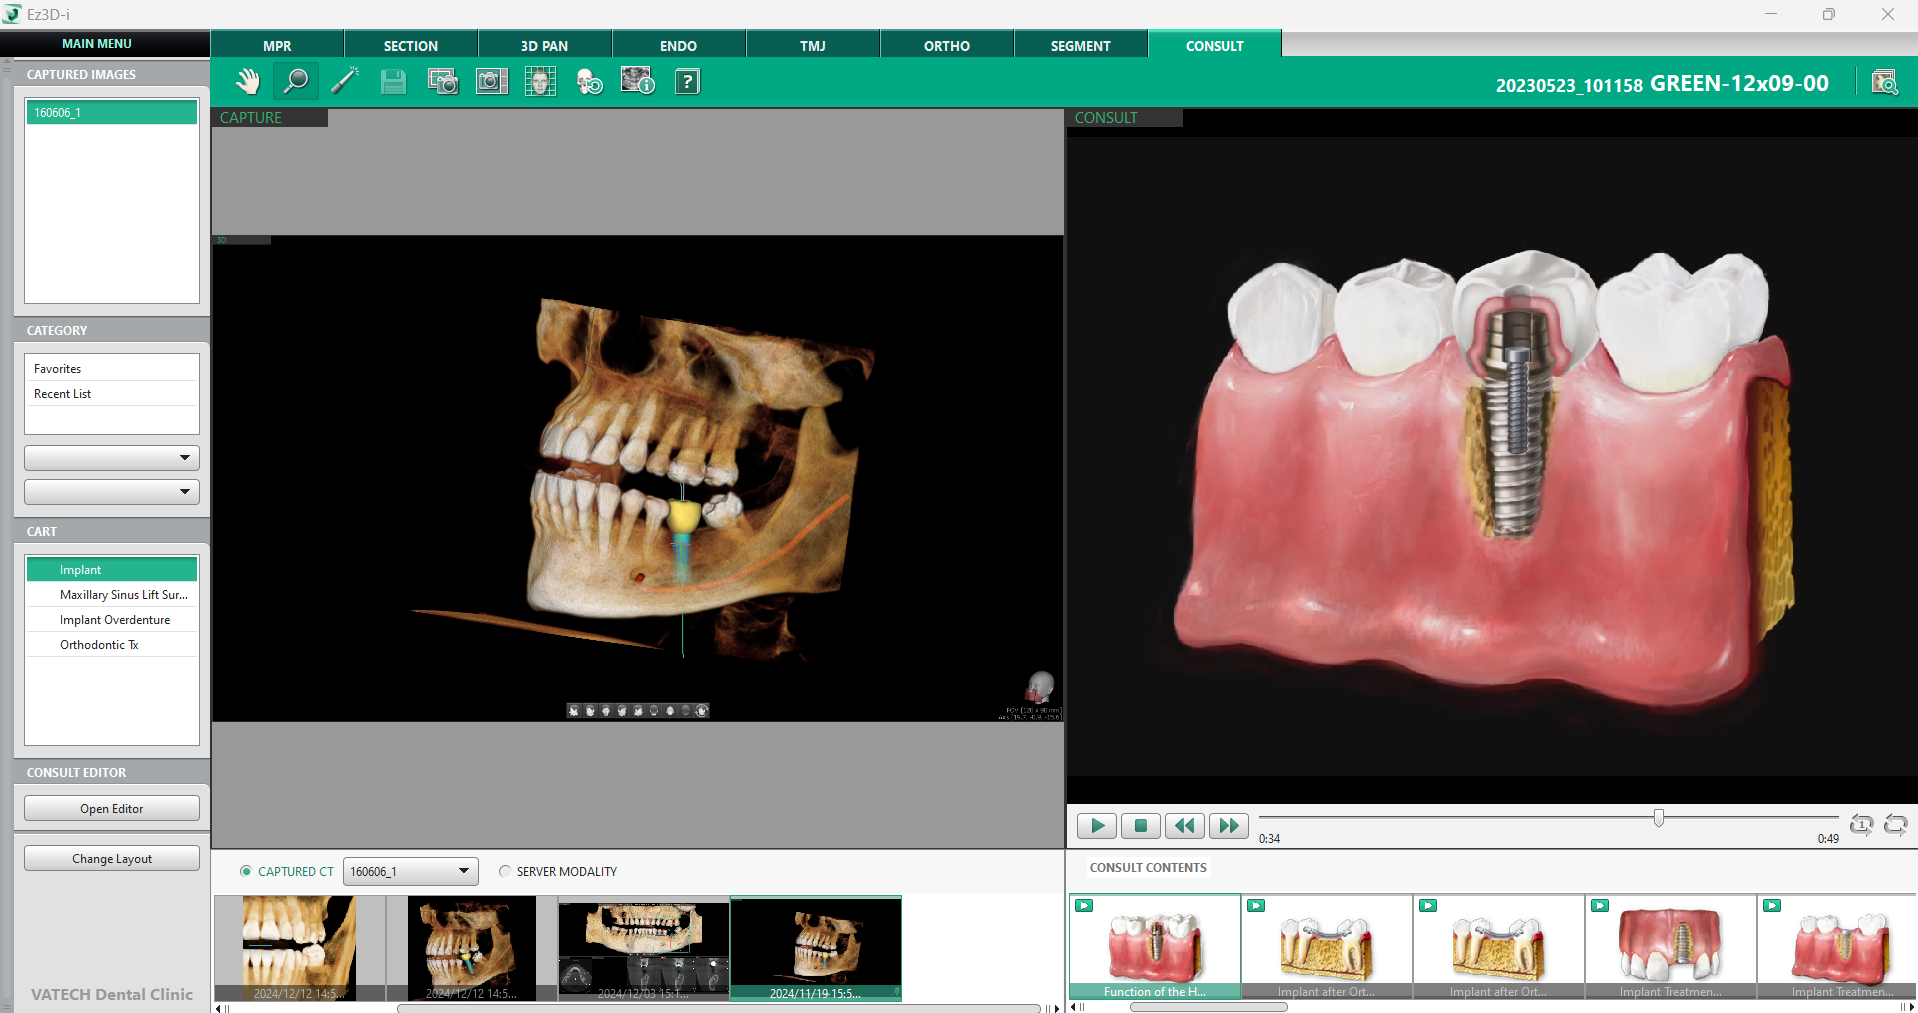

Importanța CBCT în planificarea implanturilor și modul în care software-ul Ez3D-i facilitează trasarea canalului mandibular, analiza densității osoase și măsurarea distanțelor necesare pentru o plasare optimă au fost abordate în articolul CBCT în implantologie: de la diagnostic la planificare detaliată.

Articolul de astăzi, va puncta următoarea etapă a procesului implantologic: plasarea efectivă a implantului în locul dintelui 36. Vom explora modul în care software-ul Ez3D-i permite alegere dimensiunii optime a implantului, verificarea poziționării acestuia și efectuarea ajustărilor necesare pentru un rezultat predictibil.

În următoarele rânduri vom explora în detaliu funcționalitățile cheie ale software-ului Vatech, Ez3D-i:

1. Inserarea Implantului

Procesul de inserare al unui implant într-o imagine 3D este intuitiv – odată ce etapa de pregătire este finalizată și zona destinată implantului este măsurată corect, se poate face click dreapta pe linia de măsurare și selecta „Insert Implant”.

Inteligența artificială a software-ului va procesa măsurătorile și va oferi 3 opțiuni de dimensiuni diferite de implanturi – una ușor mai mică decât distanța măsurată, una perfect ajustară și una ușor mai mare, ceea ce permite alegerea celei mai potrivite variante. De asemenea, instrumentul AI va sugera implanturi din tab-ul de favorite, asigurând astfel un flux de lucru eficient și personalizat.

Odată selectată dimensiunea dorită printr-un click stânga, modelul implantului apare instantaneu în imaginea 3D, facilitând plasarea și verificarea sa în timp real.

2. Verificarea poziției implantului

a. Setarea axei MPR

Funcția Set MPR Axis este un instrument esențial pentru verificarea poziționării corecte a implantului, oferind o metodă rapidă și eficientă de analiză a sănătății osoase și a plasării implantului în raport cu structurile adiacente.

Printr-un simplu click dreapta pe implant și selectarea opțiunii „Set MPR Axis” din fila MPR, software-ul realiniază automat toate planurile imagistice conform poziției implantului. Această funcție oferă medicului o perspectivă detaliată asupra implantului în raport cu densitatea osoasă și permite ajustarea rapidă a poziției înainte de finalizarea procedurii.

b. Densitatea osoasă a implantului

O evaluare corectă a densității osoase este esențială pentru succesul unui implant dentar. Deși am discutat în acest articolul despre numeroasele instrumentele dedicate analizării densității osoase, acest instrument specific oferă o verificare finală a compatibilității implantului cu osul în care urmează să fie plasat.

Disponibil în tab-ul 3D Pan, instrumentul poate fi activat prin selectarea opțiunii „Change Layout” din colțul stâng inferior al ecranului și alegerea unei configurații care include fereastra „Implant Bone Density”.

După selectarea implantului dorit printr-un click stânga, software-ul va genera automat un model grafic al acestuia, suprapus cu o reprezentare coloristică a densității osoase, conform scalei D1 – D5. Această reprezentare vizuală permite medicului să evalueze în detaliu structura osoasă din jurul implantului, identificând eventualele zone cu densitate scăzută care ar putea necesita proceduri suplimentare, cum ar fi augmentarea osoasă. Modelul poate fi rotit și analizat din orice unghi, oferind o perspectivă completă asupra viabilității implantului.

c. Informații despre implant

Un alt aspect crucial în procesul de verificare este accesul facil la toate informațiile relevante despre implant. Vizualizarea MPR oferă opțiunea de afișare detaliată a caracteristicilor implantului, facilitând organizarea și planificarea procedurii. Printr-un simplu click dreapta pe implant și selectarea opțiunii „Show Info”, se pot accesa toate detaliile esențiale, inclusiv tipul implantului, dimensiunea, linia de produse și alte specificații tehnice.

Această funcție este deosebit de utilă pentru coordonarea echipei medicale, deoarece permite o gestionare clară a fiecărui pas din procedură. Odată ce informațiile nu mai sunt necesare, ele pot fi ascunse rapid printr-un click nou pe implant și selectarea opțiunii „Hide Info”.

SFAT UTIL: Gestionarea mai multor implanturi

În cazul pacienților cu implanturi multiple plasate în imaginea 3D, Ez3D-i oferă o secțiune specială numită “Implant” care este situată în tab-ul 3D PAN, în colțul din stânga sus. Prin intermediul acestei funcționalități navigarea între implanturi este simplificată, evitând confuzia și economisind timp în procesul de analiză și planificare. |

3. Tab-ul „Proprietăți Implant”

Unul dintre cele mai importante aspecte ale procesului de inserare a implanturilor este posibilitatea de personalizare și ajustare a fiecărui detaliu pentru a obține rezultate optime. Tab-ul „Proprietăți Implant” oferă o interfață intuitivă prin care pot modifica numeroși parametri ai implantului, asigurând o adaptare precisă la anatomia pacientului.

Accesarea acestui tab se face simplu, prin click dreapta pe implant și selectarea opțiunii ”Property”. Prima opțiune disponibilă în acest tab este alegerea între un implant unic sau plasarea mai multor implanturi simultan. Această funcționalitate simplifică procesul de restaurare dentară, permițând optimizarea distribuției implanturilor în funcție de necesitățile pacientului.

În plus, software-ul afișează clar dintele pe care urmează să fie inserat implantul, oferind posibilitatea de a modifica numărul dintelui în funcție de poziția acestuia. După confirmarea setărilor prin apăsarea butonului „OK”, modelul de coroană se va ajusta automat, reflectând noile specificații.

Din partea stângă a ferestrei, se pot activa sau dezactiva vizualizarea unor elemente esențiale, precum implantul, ghidul implantului, traiectoria acestuia și coroana dentară. Aceste opțiuni sunt complet personalizabile, inclusiv din punct de vedere al culorii, permițând o reprezentare vizuală clară și adaptată preferințelor utilizatorului.

În imediata apropiere a acestor opțiuni, software-ul permite selectarea producătorului și a liniei de implanturi preferate. Pentru a eficientiza procesul, se poate seta o variantă implicită, astfel încât AI-ul să recomande automat implanturile favorite la următoarele planificări.

Baza de date include informații actualizate despre toți producătorii importanți de implanturi, iar lista este periodic revizuită și completată prin colaborarea cu distribuitorii autorizați. În tabelul din dreaptă a ferestrei, software-ul afișează implanturile disponibile, corespunzătoare producătorului și liniei selectate, facilitând astfel alegerea optimă pentru fiecare pacient.

4. Opțiuni pentru plasarea implantului

În cazul nostru, am utilizat opțiunea de plasare a implantului prin măsurarea lungimii, însă software-ul Ez3D-i oferă mai multe metode alternative de inserare a implantului, inclusiv prin asistență AI.

Pentru utilizarea acestor opțiuni inteligente, se poate accesa tab-ul MPR, din meniul „Simulare” din colțul stâng sus și selecta “Insert Implant”. Această acțiune va deschide automat fereastra de proprietăți a implantului, oferind posibilitatea de a configura parametrii doriți.

În funcție de necesități, se poate alege dintre opțiunile: Plasare inteligentă, Plasare pe axă sau Plasare la punctul de click, situate în partea de jos.

Prin selectarea opțiunii “Plasare inteligentă” software-ul inserează automat implantul pe baza numărului dintelui selectat. În cazul în care se optează pentru “Plasare pe axă” implantul este poziționat automat în funcție de o axă predefinită, iar opțiunea „Plasare la punctul de click” va transforma cursorul mouse-ului într-un instrument de inserare, plasând implantul exact în punctul în care se face click.

Este important de menționat că opțiunea de plasare prin măsurarea lungimii nu poate fi realizată folosind butonul „Inserare Implant”, ci necesită setarea manuală a parametrilor în software.

5. Ajustări și pregătirea implantului pentru CAD/CAM

După ce implantul a fost plasat și poziționat corect, urmează etapa finală de ajustare și pregătire pentru integrarea cu sistemele CAD/CAM. Această etapă este esențială pentru a obține o restaurare precisă și adaptată perfect pacientului.

Software-ul Ez3D-i oferă multiple opțiuni pentru ajustarea fină a implantului, permițând modificarea poziției, dimensiunea și orientarea acestuia în funcție de necesitățile clinice. Pentru o precizie maximă, se poate utiliza controller-ul virtual, un instrument care permite modificări detaliate asupra poziției implantului. Există două tipuri de controllere – unul dedicat implantului în sine și altul destinat coroanei. Accesarea acestora se face simplu, printr-un click dreapta pe componenta dorită și selectarea opțiunii „Afișare controller”.

În cazul în care dimensiunea inițială a implantului nu corespunde perfect cu anatomia pacientului, software-ul oferă și opțiunea de redimensionare. Prin click dreapta pe implant și selectarea opțiunii “Edit implant”, se poate ajusta lungimea, dimensiunea ocluzală și dimensiunea apicală. Modificările sunt aplicate automat, în conformitate cu linia de implant aleasă.

Odată ce toate ajustările au fost realizate, urmează exportarea modelului pentru integrarea cu sistemele CAD/CAM. Aceasta se face rapid, accesând meniul principal și selectând “Export Surface Model”. Caseta de dialog ghidează întregul proces, oferind opțiuni pentru formatul fișierului, nivelul de netezire, dimensiunea și tipul de date care urmează să fie exportate.

Această etapă finală asigură o restaurare dentară precisă și un rezultat predictibil, optimizând fluxul de lucru în cabinetul stomatologic și îmbunătățind experiența pacientului.

6. Tab-ul „Consultare”

Pentru mulți pacienți, ideea unei intervenții implantologice poate fi intimidantă, de aceea comunicarea clară și eficientă a detaliilor procedurii este esențială. Software-ul Ez3D-i include tab-ul “Consult”, un instrument dedicat sprijinirii procesului de comunicare dintre medic și pacient. Acest tab este conceput pentru a oferi pacienților o înțelegere detaliată a tratamentului propus.

În partea stângă a ferestrei sunt afișate capturile de ecran, imaginile și materialele pregătite de medic, în timp ce în partea dreaptă sunt disponibile videoclipuri educaționale furnizate de Vatech. Baza de date conține peste 250 de videoclipuri didactice, grupate în funcție de subiect, oferind pacienților explicații vizuale despre etapele procedurii implantologice. Prin intermediul acestor resurse, pacienții pot înțelege mai bine importanța fiecărei etape a tratamentului, reducând anxietatea și sporind încrederea în procesul medical.

Integrarea tab-ului „Consultare” în fluxul de lucru al cabinetului reprezintă o metodă eficientă de a educa pacienții și de a-i ajuta să ia decizii informate. Acest aspect nu doar că îmbunătățește experiența pacientului, dar contribuie și la creșterea ratei de acceptare a planurilor de tratament, facilitând colaborarea dintre medic și pacient.